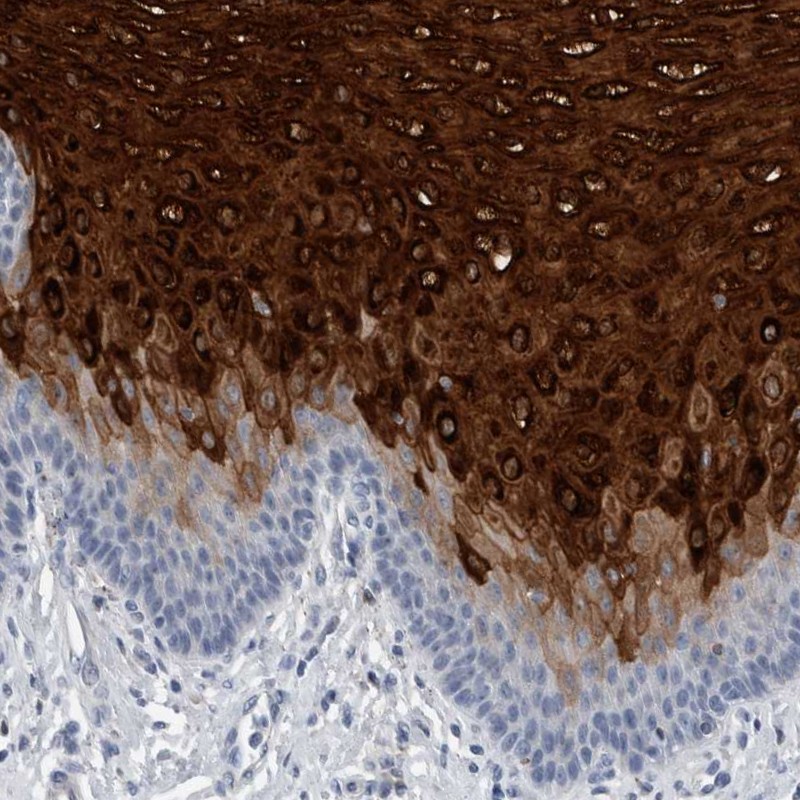

Immunohistochemistry analysis in human esophagus and stomach tissues using Anti-CRNN antibody. Corresponding CRNN RNA-seq data are presented for the same tissues.